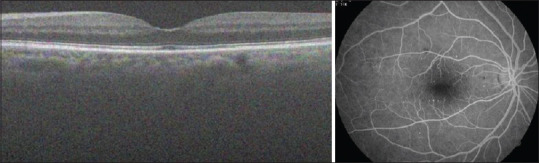

Abstract Image